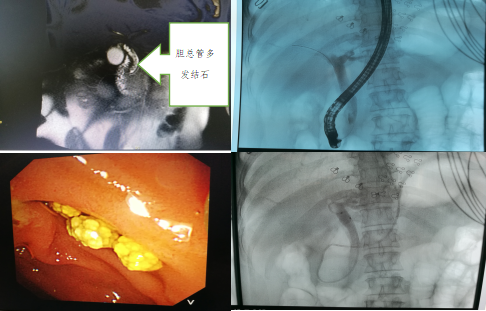

我院诊治的典型病例

病例1:急性胆源性胰腺炎,结石坎顿于十二指肠乳头,十二指肠乳头肿大,消化科为患者行急诊ERCP术取石,患者术后三天痊愈出院。

病例2:胆总管多发结石,行ERCP术胆道取石+鼻胆管引流术,术后2天出院。